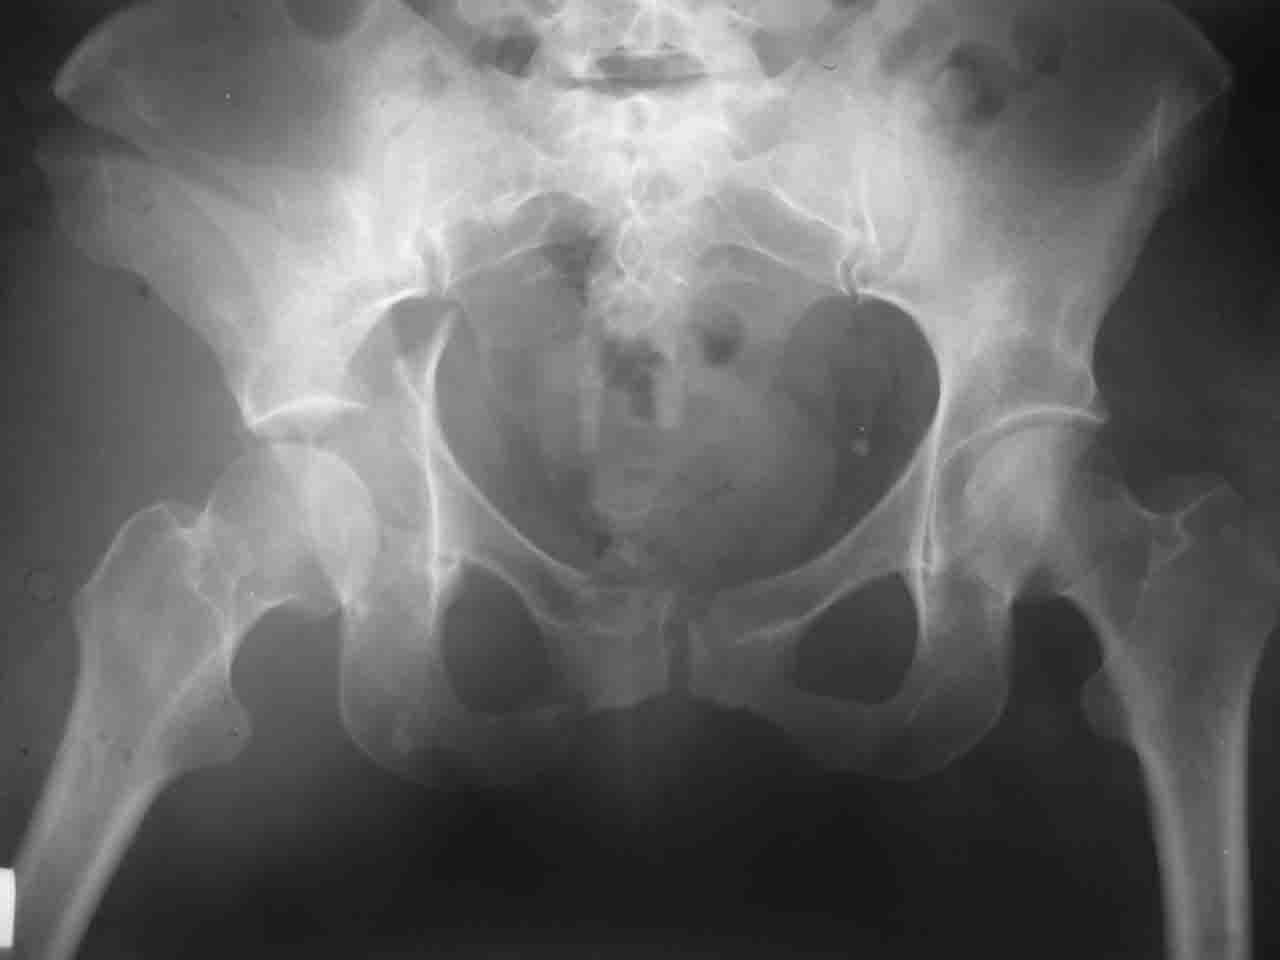

Интерес к реконструкции вертлужной впадины у меня появился довольно-таки давно, но до недавнего времени как-то не ощущалась готовность к практической реализации, а местный подход достаточно консервативен - перелом срастется,

а далее будет видно. Такую точку зрения я не разделяю, поэтому через конференции,ортофорум и свои случаи пытаюсь практически и теоретически *продвинуть* для себя тему реконструкции вертлужной впадины.

Логика подсказывает, что все-таки лучше иметь анатомически полноценную впадину, хотя ранее упоминалось состояние вторичной конгруэнтности и одно наблюдение у меня есть, когда у больного с полностью нарушенной анатомией впадины и подвывихом головки бедра кзади и кверху боли отсутствовали при относительно достаточном для стиля жизни больного объёме движений. Но это только одно наблюдение и кроме перелома впадины у этогобольного была и тяжелая ЧМТ в анамнезе. Основываясь на формулировке структуры ацетабулюм Э. Летурнеля - как перевернутой буквы Y, впадина для полноценной функции сустава должна иметь сферичность, соответствующую размеру головки бедра и если один из компонентов в дефиците, то функциональные последствия рано или поздно проявятся.

Сложностью, ассоциативностью характера перелома, я бы с радостью воспользовался мининвазивной перкутанной фиксацией винтами, но боюсь, что результат был бы ещё хуже, техникой непрямой репозиции перелома не владею, поэтому пытаясь получить анатомичную впадину приходится широко открывать, по крайней мере пока, а дальше буду пытаться уменьшать пространство...

Илеофеморальный доступ не совсем передний и сравнительно с илеоингвинальным, и Кохера-Лангенбека открывает весь наружный таз кроме самых передних отделов лонных костей, фиксацию которых я не ставил в задачу. Обширность диссекции, большая длительность операции и более высокий риск гетерооссификации - отрицательные моменты в обмен на возможность легче ориентироваться.